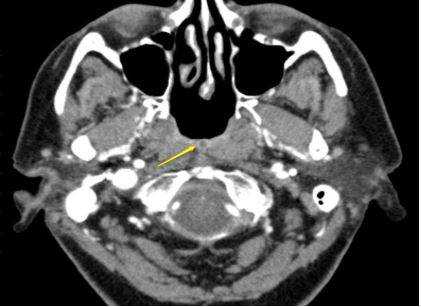

Фото - Рак носоглотки, с распространением на окологлоточное пространство (стрелкой указана зона инвазии)